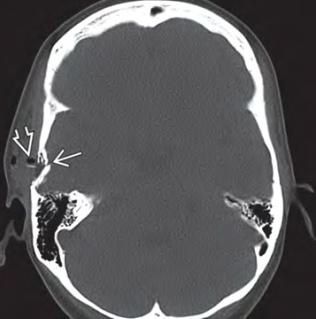

Вдавлені переломи стінок лобових пазух

Іноді, при травматичних ушкодженнях лобової кістки, може виникати так званий вдавлений перелом зовнішньої та / або внутрішньої стінок лобової (фронтальної) пазухи.

Вона розташовується в області надбрів’я, є повітроносною пазухою, її стінки є досить тонкими та досить легко ламаються, що проявляється досить помітним вдавлення в травмованій області, яке сприймається як серйозний косметичний недолік.

Діагностика

Вдавлений перелом може бути виявлений при хірургічній обробці рани, за допомогою рентгенографії кісток черепа, і краще за все діагностується при виконанні комп’ютерної томографії голови.